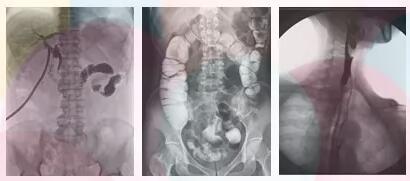

方面三、子宮輸卵管造影,優(yōu)選動態(tài)平板dr

采集面積大,一次曝光即可顯示整個盆腔,大幅減少觀察時間,可控的瞬時照射避免受檢者吸收過多的X線,對育齡期婦女的檢查尤為重要。實時高清點片,可以在造影劑流動的過程中完成拍片,抓拍到關鍵圖像,清楚的了解管腔的具體通暢情況及堵塞部位,對檢查及診斷有非常重要的價值。